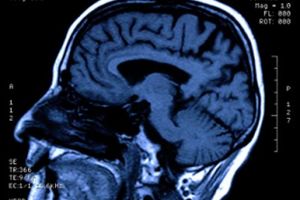

In just a few decades, the use of magnetic resonance imaging (MRI) scanners has grown tremendously. Doctors may order MRI scans to help diagnose multiple sclerosis, brain tumors, torn ligaments, tendonitis, cancer and strokes, to name just a few. An MRI scan is the best way to see inside the human body without cutting it open.

That may be little comfort to you when you're getting ready for an MRI exam. You're stripped of your jewelry and credit cards and asked detailed questions about all the metallic instruments you might have inside of you. You're put on a tiny slab and pushed into a hole that hardly seems large enough for a person. You're subjected to loud noises, and you have to lie perfectly still, or they're going to do this to you all over again. And with each minute, you can't help but wonder what's happening to your body while it's in this machine. Could it really be that this ordeal is truly better than another imaging technique, such as an X-ray or a CAT scan? What has Raymond Damadian wrought?